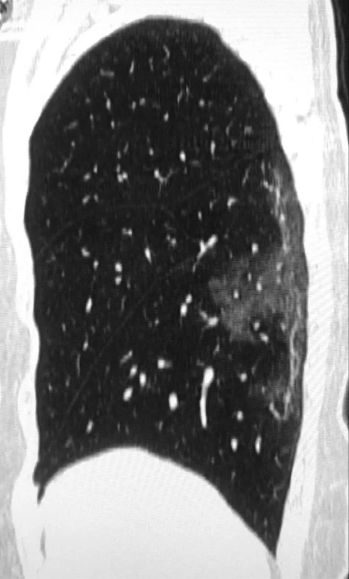

Tổn thương ở phổi của một người phụ nữ 45 tuổi ở tỉnh Tứ Xuyên, Trung Quốc dương tính với COVID-19.